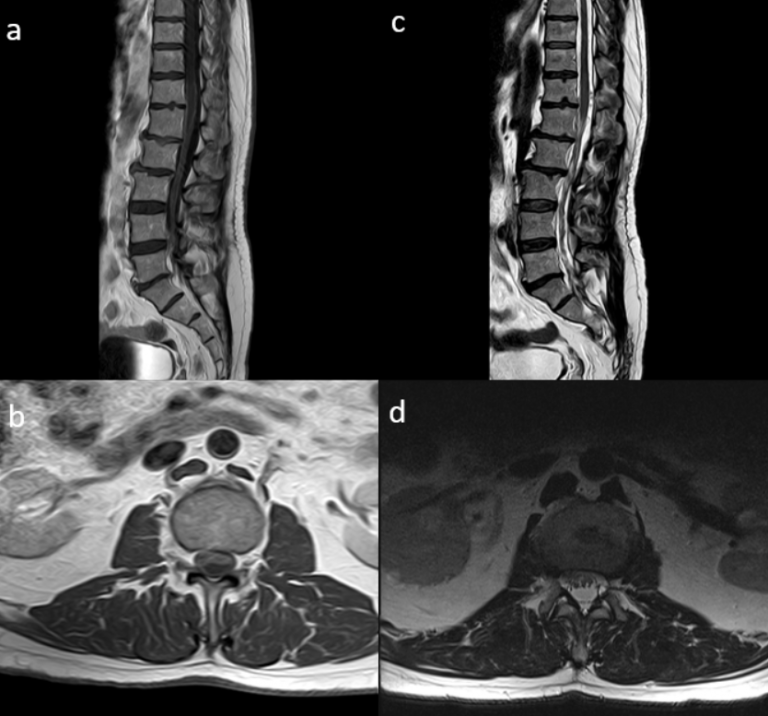

Resonancia magnética: secuencias ponderadas en T1 con gadolinio en plano axial (A), sagital (B) y coronal (C): Masa extraaxial de aspecto heterogéneo, bien definida, con un intenso realce periférico, de 42 x 41 x 38 mm (AP x TR x CC) en la línea media frontobasal. La lesión está en contacto con la lámina cribiforme y parece originarse del bulbo y tracto olfatorio izquierdo. Aisladas formaciones quísticas periféricas. Secuencia ponderada en T2 plano coronal (D): extensa área de hiperseñal T2 que se extiende por la sustancia blanca del lóbulo frontal izquierdo.